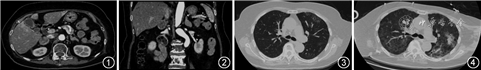

入院查血常规提示白细胞计数为8.1×109个/L,血红蛋白为122 g/L,血小板计数为79×109个/L,中性粒细胞比例为92%。尿便常规、肝肾功能、心肌损伤标志物、ESR、凝血功能正常,白蛋白为32.3 g/L,血钾为2.95 mmol/L,乳酸脱氢酶(lactate dehydrogenase,LDH)为438 U/L(正常参考值100~240 U/L),超敏C反应蛋白为1.90 mg/L(正常参考值0~3 mg/L)。糖化血红蛋白为8.60%。甲状腺功能提示总三碘甲腺原氨酸(T3)0.72 nmol/L(正常参考值0.92~2.79 nmol/L),游离三碘甲腺原氨酸(FT3) 2.73 pmol/L(正常参考值3.5~6.5 pmol/L),总甲状腺素(T4) 54.1 nmol/L(正常参考值59.1~140.6 nmol/L),游离甲状腺素(FT4) 13.90 pmol/L,促甲状腺激素(TSH) 0.09 μU/ml(正常参考值0.55~4.78 μU/ml)。肿瘤标志物提示细胞角蛋白19片段 6.32 μg/L(正常参考值<3.3 μg/L),其余均阴性。动脉血气分析(未吸氧)结果为pH值为7.522,PaO2为71.5 mmHg,PaCO2为38.9 mmHg,碳酸氢根离子为34.4 mmol/L,乳酸为2.3 mmol/L。8∶00皮质醇128.8为μg/dl(正常参考值4.4~19.9 μg/dl)、促肾上腺皮质激素(adrenocorticotropic hormone,ACTH) 404.7 ng/L(正常参考值7.2~63.3 ng/L),24尿游离皮质醇3.21×104 μg/24 h(正常参考值370~639 μg/24 h),小剂量地塞米松试验、大剂量地塞米松试验均未被抑制。肾上腺增强CT示右侧肾上腺结节,腺瘤可能大,双侧肾上腺增生可能(图1,2)。垂体增强MRI未见明显异常。胸部CT平扫(图3)示:双肺片状磨玻璃密度影,左肺上叶为著;双肺可见散在实性微结节。诊断为异位促肾上腺皮质激素综合征(ectopic adrenocorticotropic hormone syndrome,EAS),胸部CT表现不考虑恶性肿瘤,因患者无呼吸道症状及发热,未予治疗。

入院第16日(2019年10月10日)开始给予奥曲肽0.1 mg 1次/12 h皮下注射抑制ATCH水平,当日(尚未注射)患者即突发喘憋,脉氧饱和度75%,予面罩吸氧10 L/min,后无创呼吸机辅助通气,同时利尿、扩血管治疗仍恶化,予气管插管后第二日转入呼吸监护室。转入后查外周血T辅助淋巴细胞计数为51.5个/μl(正常参考值406~1 612.0个/μl),LDH为724 U/L,降钙素原(procalcitonin,PCT)为0.55 μg/L,(1, 3)-β-葡聚糖(G实验)为175.80 pg/ml(>100 ng/L为阳性),血清半乳甘露聚糖检测阴性。复查胸部CT(图4)提示双肺磨玻璃病灶及实变较前进展,伴小叶间隔轻度增厚。血清巨细胞病毒(cytomegalo virus,CMV)核酸定量(CMV-DNA)5.45×103 拷贝数/ml(正常参考值<500拷贝数/ml)。支气管肺泡灌洗液(bronchoalveolar lavage fluid,BALF)检测白细胞分类:巨噬细胞17%、中性粒细胞81%、淋巴细胞2%,镜检提示大量耶氏肺孢子菌(pneumocystis jiroveci)包囊,培养提示铜绿假单胞菌,CMV-DNA定量 6.59×105 拷贝数/ml。BALF的高通量测序:高置信度阳性指标:人细小病毒B19型(检出序列数17 141)、CMV(检出序列数81)、肺炎链球菌(检出序列数2 143 139)、丙酸棒状杆菌(检出序列数350 053)、金黄色葡萄球菌(检出序列数116 247)、肺炎克雷伯菌(8 904)、耶氏肺孢子菌(11 431)、白色念珠菌(378),中置信度阳性指标:铜绿假单胞菌(检出序列数1 416)。经中心静脉导管血培养提示人葡萄球菌,同时经外周静脉血培养阴性,考虑此病原为污染可能。结合PCT水平、BALF病原结果和影像学,考虑细菌、CMV和肺孢子菌混合的肺部感染、CMV血症。